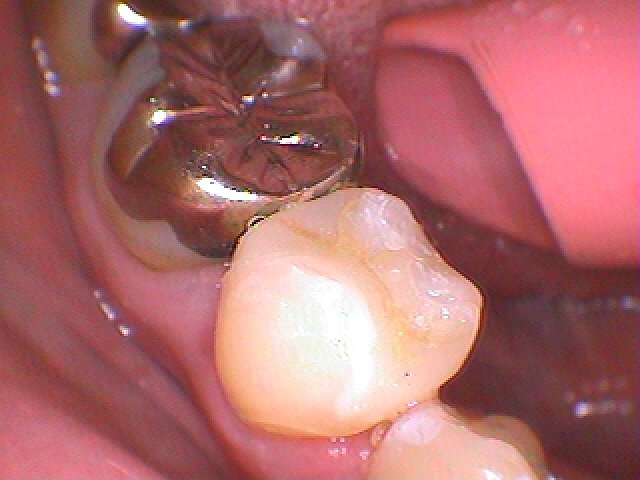

セレックセラミックにて修復しています

本来の歯のようにきれいに仕上がりました